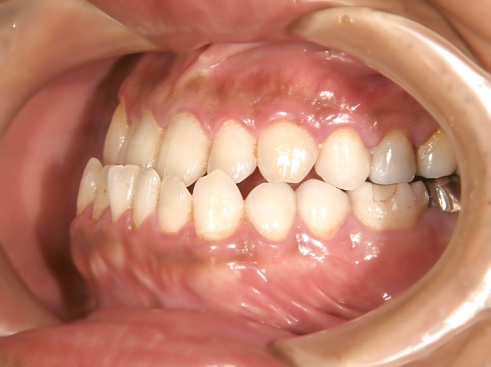

治療後

治療前